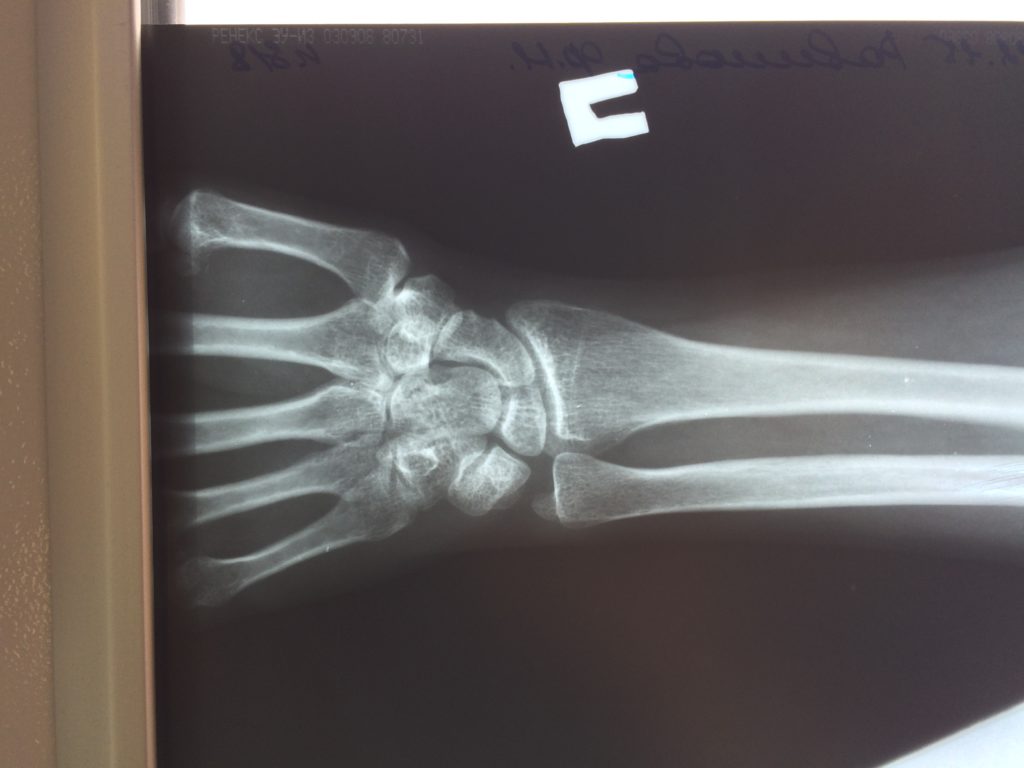

Операция - открытая репозиция, остеосинтез лучевой кости пластиной с костной ксенопластикой материалом "Остеоматрикс". На контрольных снимках в три месяца имеется консолидация перелома, миграции фиксатора нет, имеется остеоинтеграция ксенопластического материала.

Отдаленные результаты через 3 (три) месяца: